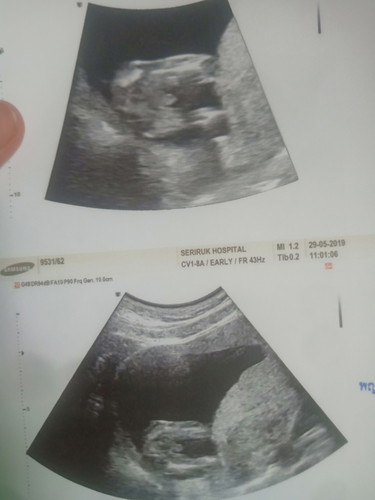

รูปซาวร์

แบบนี้ผู้ชายหรือผู้หญิงคะ

ผู้ชาย 100% ค่ะ จู๋ยื่นออกมาชัดมากค่ะ เหมือนบ้านนี้เลยค่ะ จู๋ชี้เลยค่ะ 😆😆😆😆

ชายค่ะ ชัดเจนมาก จู๋น้อยชี้โด่เลย

ผู้ชายแน่นอนคะแม่ โชว์ชัดมากกก 😂

ชายค่ะ จู๋โผล่เห็นชัดเลย

น้องผู้ชายจ้า ชัดเลย